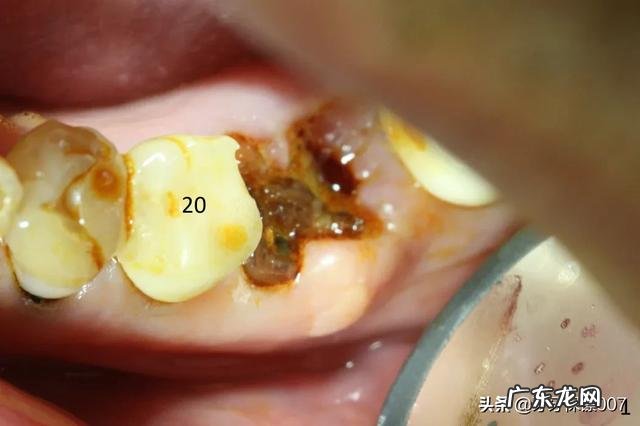

牙齿坏了很多,为什么会引起疼痛?牙体组织发生细菌感染时,其硬组织就会逐渐崩解 。当累及牙神经时,就会发生牙髓炎,急性牙髓炎疼痛比较剧烈,可以牵涉到一侧面部、头部不适,不能够明确定位 。若是没有及时处理,大多会转变为慢性牙髓炎,就会引起反复疼痛 。